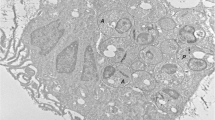

Histology

Histological features of the skin of diseased dogs (Group A and B) were previously described elsewhere [7]. Briefly, normal-looking skin of dogs from Group B was more frequently inflamed than normal-looking skin of dogs from Group A (78.6% and 27.3%, respectively; Fisher’s exact test, P = 0.017). The perivascular to interstitial inflammatory pattern was more common in clinically-lesioned skin from dogs from Group B than in clinically-lesioned skin from dogs from Group A (71.4% and 18.2%, respectively; Fisher’s exact test, P = 0.015). On the other hand, nodular to diffuse pattern with granuloma formation was more common in clinically-lesioned skin from dogs from Group A than in clinically-lesioned skin from dogs from Group B (36.4% and 0%, respectively; Fisher’s exact test, P = 0.017).